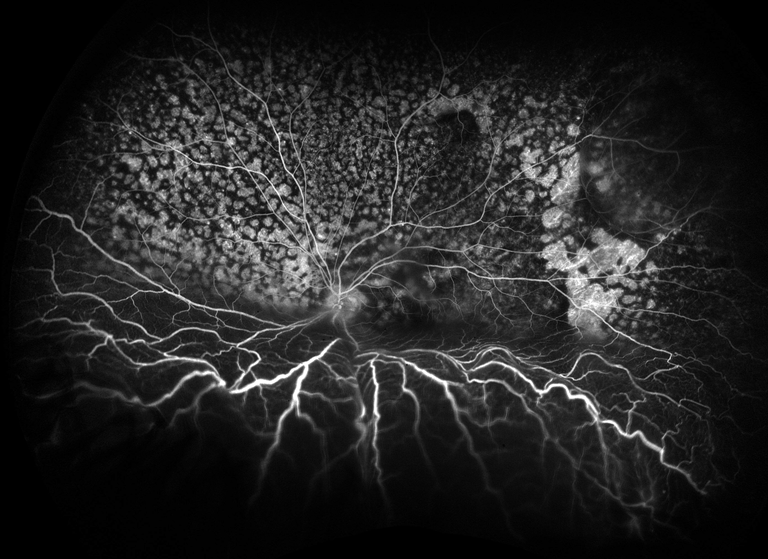

Serous Detachment

Presented by David Miller, BSc, CRAThis photograph received Honorable Mention in the category "Retinal Fluorescein Angiography" and was displayed at the 2024 ASCRS/OPS Society Exhibit.